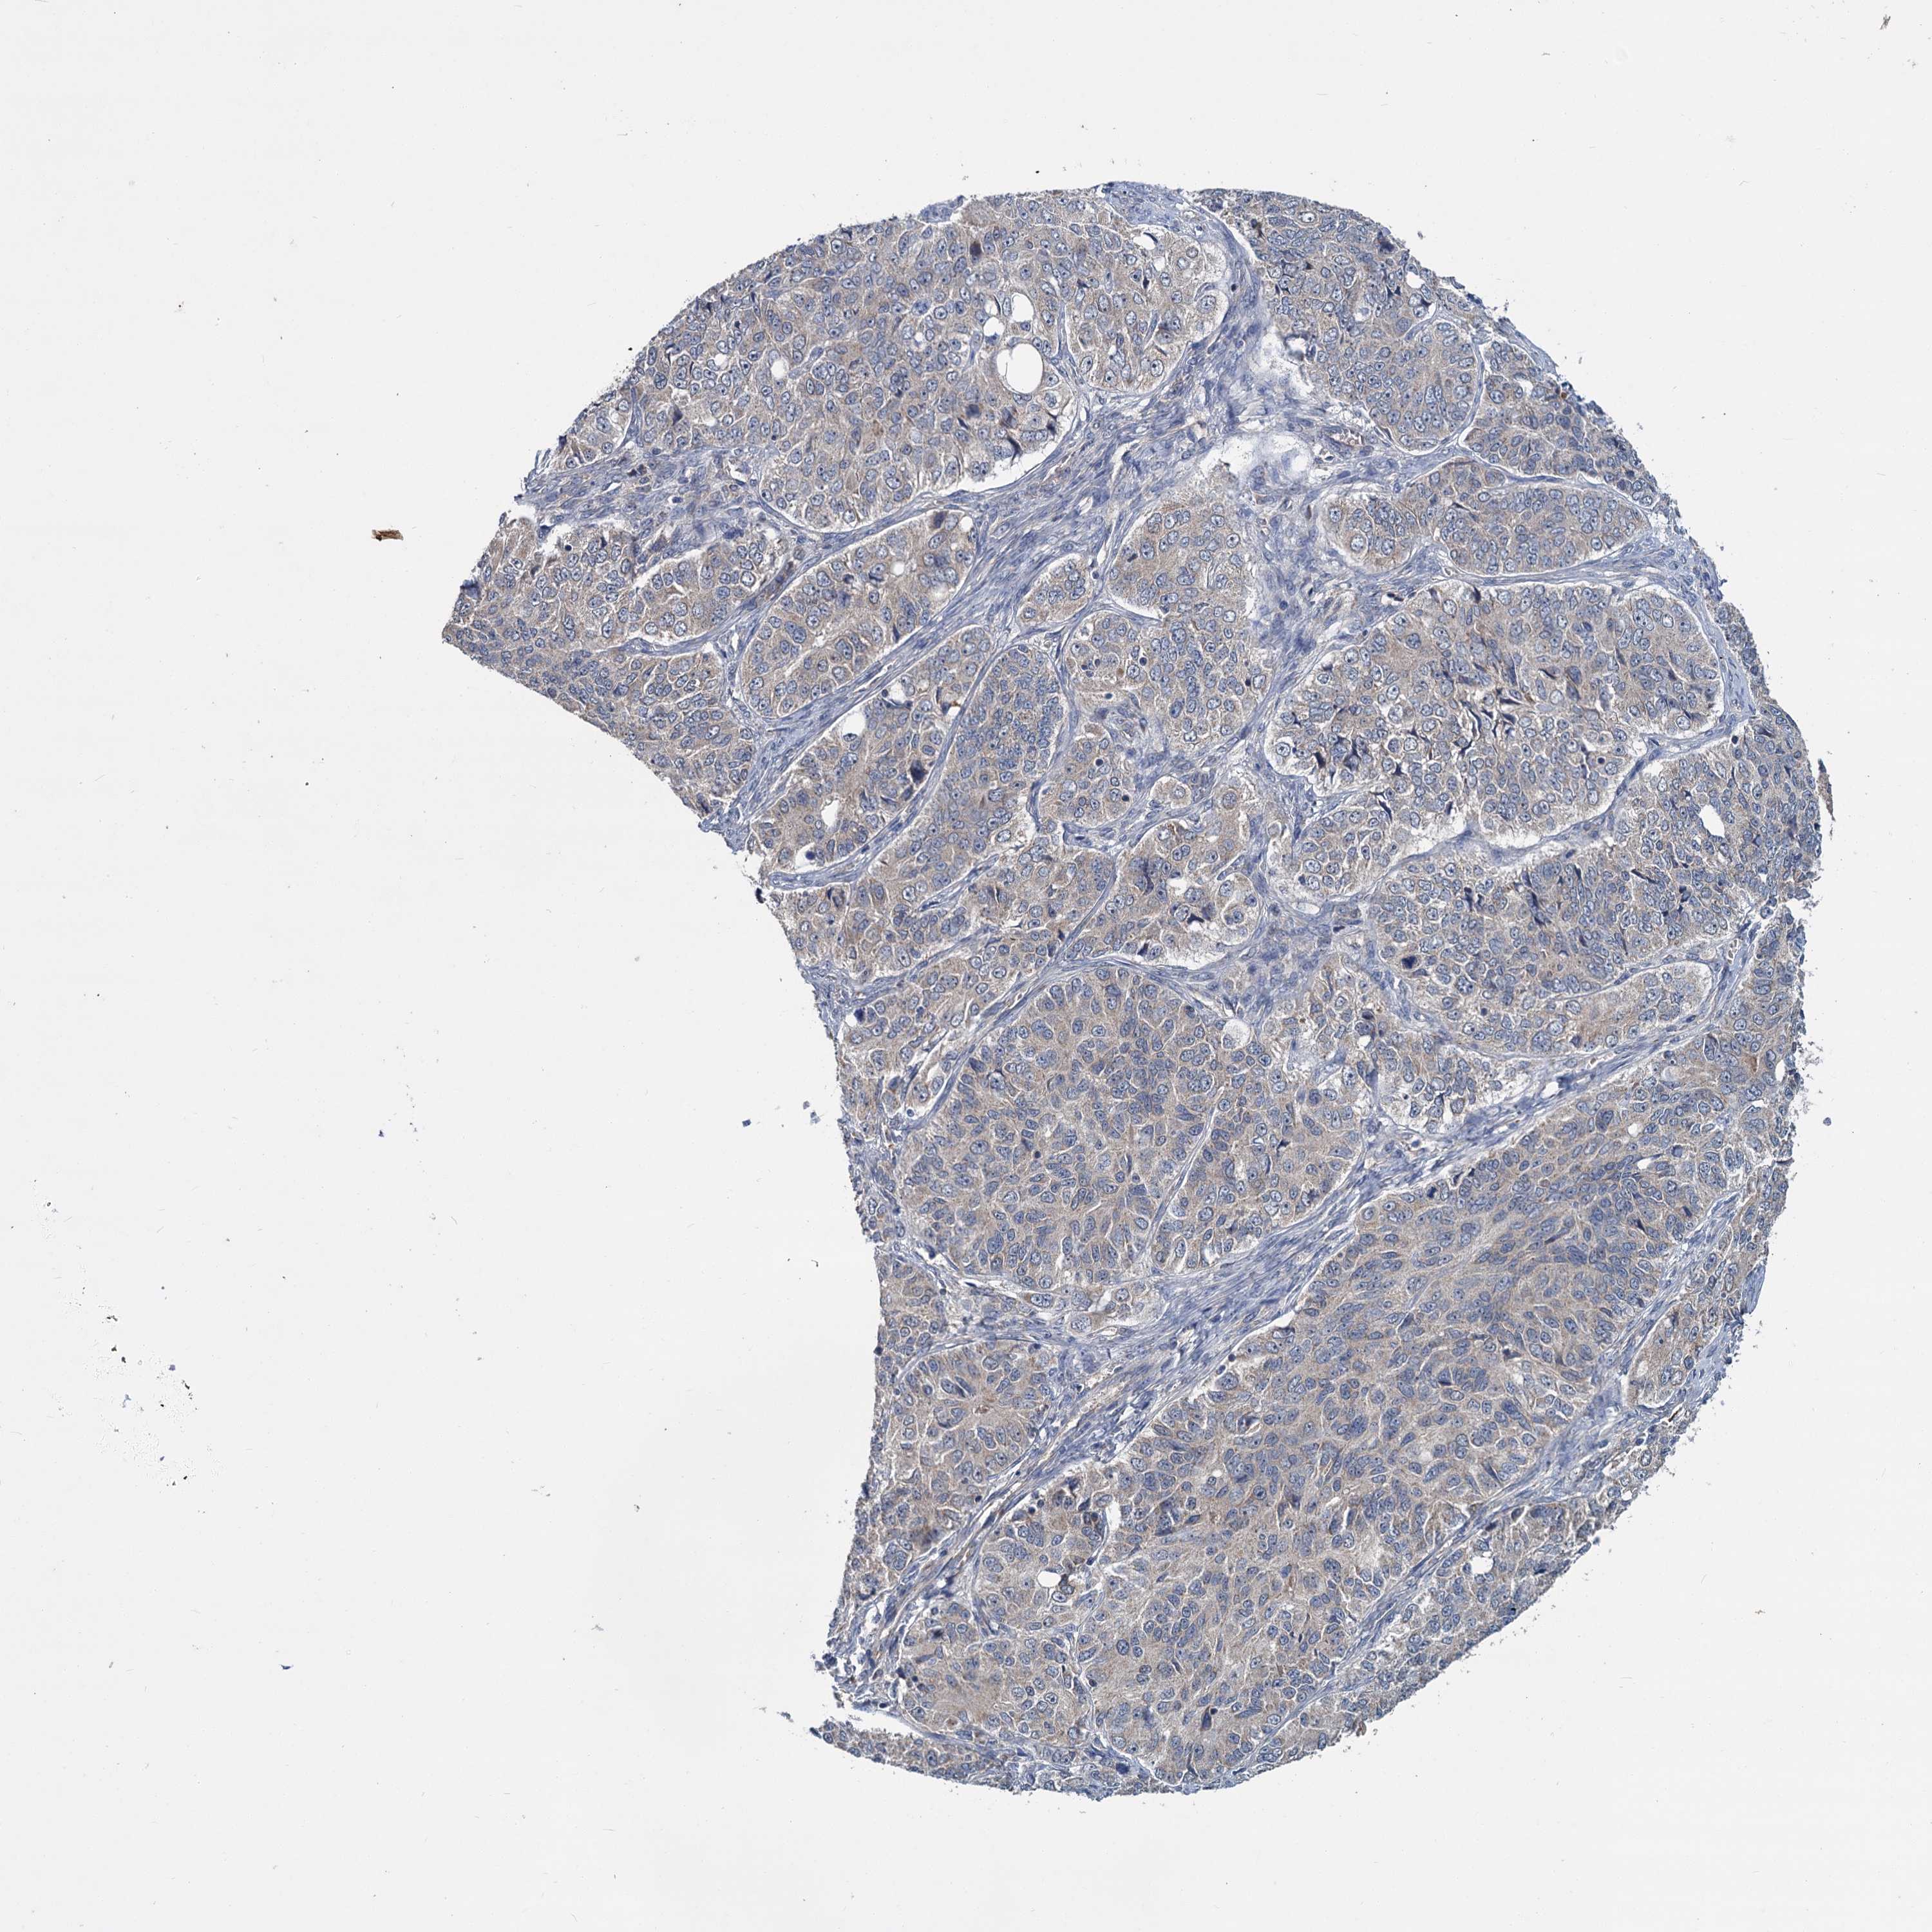

OVARIAN CANCER - Protein expressioni

A mouse-over function shows sample information and annotation data. Click on an image to view it in a full screen mode. Samples can be filtered based on level of antibody staining by selecting one or several of the following categories: high, medium, low and not detected. The assay and annotation is described here.

Note that samples used for immunohistochemistry by the Human Protein Atlas do not correspond to samples in the TCGA dataset.

Antibody stainingi

Antibody staining in the annotated cell types in the current human tissue is reported as not detected, low, medium, or high, based on conventional immunohistochemistry profiling in selected tissues. This score is based on the combination of the staining intensity and fraction of stained cells.

Each image is clickable and will lead to virtual microscopy that enables deeper exploration of all samples and also displays staining intensity scores, fraction scores and subcellular localization as well as patient and tissue information for each sample.

Antibody HPA039015

Antibody HPA039016

Cystadenocarcinoma, serous, NOS